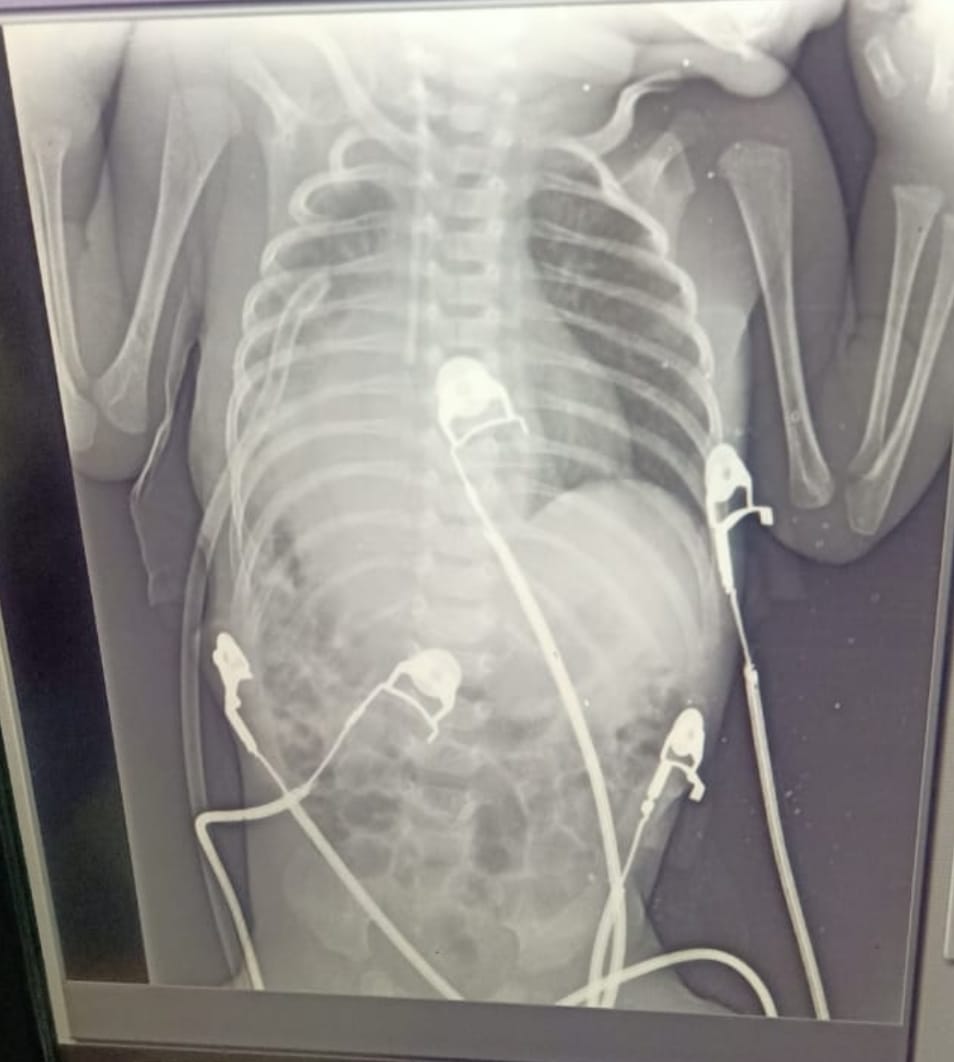

وأضاف أنه تم عمل عملية فصل لإندماج كبدي رئوي (HPF)، وهو عيب خلقى نادر يتكون من فتق بالحجاب الحاجز على الجهه اليمنى، مع اندماج نسيجى وعائي بين الكبد الموجود فى الفتق والرئة اليمنى، والأطفال الذين يعانون من هذه الحالة لديهم توقعات طبية سيئة نسبيًا، تم حجز الحاله بتشخيص فتق بالحجاب الحاجز، وتم اكتشاف التصاق كامل ما بين الكبد والرئة على الجهه اليمنى،و تم إجراء فصل جراحى جزئي ما بين الكبد والرئة اليمنى بمساعده المنظار الجراحي، حيث قد يؤدي الفصل الكامل إلى مضاعفات كارثية بسبب الاندماجات الوعائية الأساسية بين الكبد والرئة، وتعد هذة الحالة هي رقم ٢٤ التي يتم اجراؤها بنجاح على مستوى العالم.